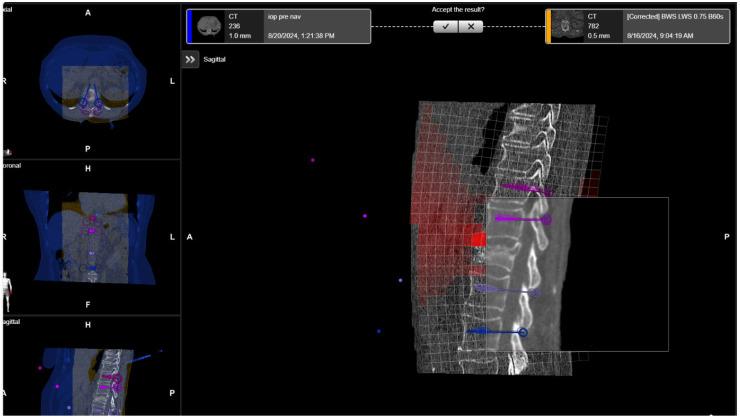

The aim of this study is to present the initiation of robotic-guided (RG) spine surgery into routine clinical care at a single center with the use of intraoperative CT (iCT) automatic registration-based navigation. The workflow included iCT with automatic registration, fusion with preoperative imaging, verification of preplanned screw trajectories, RG introduction of K-wires, and the insertion of pedicle screws (PSs), followed by a control iCT scan. All patients who underwent RG implantation of pedicle screws using the Cirq robotic arm (BrainLab, Munich, Germany) in the thoracolumbar spine at our department were included in the study. The accuracy of the pedicles screws was assessed using the Gertzbein-Robbins scale (GRS). In total, 108 patients (60 female, mean age 68.7 ± 11.4 years) in 109 surgeries underwent RG PS placement. Indications included degenerative spinal disorders ( = 30 patients), spondylodiscitis ( = 24), tumor ( = 33), and fracture ( = 22), with a mean follow-up period of 7.7 ± 9 months. Thirty-seven cases (33.9%) were performed percutaneously, and all others were performed openly. Thirty-three operations were performed on the thoracic spine, forty-four on the lumbar and lumbosacral spine, thirty on the thoracolumbar, one on the cervicothoracic spine, and one on the thoracolumbosacral spine. The screws were inserted using a fluoroscopic (first 12 operations) or navigated technique (latter operations). The mean operation time was 228.8 ± 106 min, and the mean robotic time was 31.5 ± 18.4 min. The mean time per K-wire was 5.35 ± 3.98 min. The operation time was lower in the percutaneous group, while the robot time did not differ between the two groups. Robot time and the time per K-wire improved over time. Out of 688 screws, 592 were GRS A screws (86.1%), 54 B (7.8%), 22 C (3.2%), 12 D (1.7%), and 8 E (1.2%). Seven screws were revised intraoperatively, and after revision, all were GRS A. E screws were either revised or removed. In the case of D screws, screws located at the end of the construct were revised, while so-called in-out-in screws in the middle of the construct were not revised. Brainlab's Cirq Robotic Alignment Module feature enables placement of pedicle screws in the thoracolumbar spine with high accuracy. A learning curve is shown through improvements in robotic time and time per K-wire.

本研究的目的是介绍在单一中心将机器人引导(RG)脊柱手术引入常规临床护理,采用术中CT(iCT)基于自动配准的导航技术。工作流程包括iCT自动配准、与术前影像融合、预规划螺钉轨迹验证、RG引导下克氏针置入以及椎弓根螺钉(PS)植入,随后进行对照iCT扫描。本研究纳入了在我们科室接受使用Cirq机器人手臂(德国慕尼黑BrainLab公司)在胸腰椎进行RG椎弓根螺钉植入的所有患者。使用Gertzbein-Robbins量表(GRS)评估椎弓根螺钉的准确性。总共109例手术中的108例患者(60例女性,平均年龄68.7±11.4岁)接受了RG PS置入。适应证包括退行性脊柱疾病(n = 30例患者)、脊椎间盘炎(n = 24)、肿瘤(n = 33)和骨折(n = 22),平均随访期为7.7±9个月。37例(33.9%)为经皮手术,其余均为开放手术。胸椎手术33例,腰椎和腰骶椎手术44例,胸腰椎手术30例,颈胸椎手术1例,胸腰段手术1例。螺钉采用透视技术(前12例手术)或导航技术(后序手术)置入。平均手术时间为2(28.8±106)分钟,平均机器人操作时间为31.5±18.4分钟。每根克氏针的平均时间为5.35±3.98分钟。经皮组的手术时间较短,而两组的机器人操作时间无差异。机器人操作时间和每根克氏针的时间随时间有所改善。在688枚螺钉中,592枚为GRS A级螺钉(86.1%),54枚为B级(7.8%),22枚为C级(3.2%),12枚为D级(1.7%),8枚为E级(1.2%)。7枚螺钉在术中进行了翻修,翻修后均为GRS A级。E级螺钉要么进行了翻修,要么被取出。对于D级螺钉,位于结构末端的螺钉进行了翻修,而结构中间的所谓进出式螺钉未进行翻修。Brainlab公司的Cirq机器人对准模块功能能够高精度地在胸腰椎置入椎弓根螺钉。通过机器人操作时间和每根克氏针时间的改善显示出学习曲线。